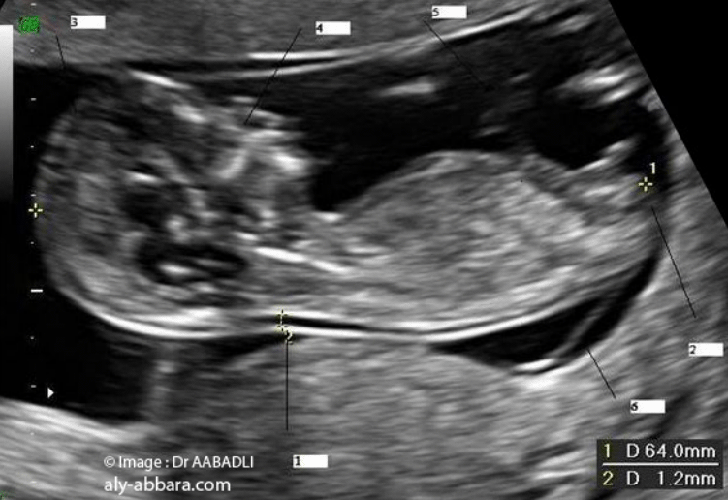

L'échographie de la clarté nucale est un test de dépistage qui permet d'évaluer le risque que votre bébé soit atteint du syndrome de Down (trisomie 21) BabyCenter Canada BabyCenter Canad ;468 Down syndrome) », Prenat Diagn, vol 30, no 1, 10, p 5764 (PMIDSpé chir et gynécoobst, s21DP 34,02 EUR Spé chir et gynécoobst, s21DP OPTAM 37,05 EUR Spé chir et gynécoobst, non conventionné 34,02 EUR Il s'agit de la choriocentèse, qui consiste à prélever un très petit fragment du placenta (villosités) Ce geste est réalisé entre 10 et 12 semaines d' aménorrhée , en cas de fort

Clarté nucale prix La clarté nucale est donc tjrs mesurée entre 35 et 39mmTout le reste est tjrs tout à fait normal Je n aurai pas de biopsie car je suis sous aspegic et qu avec mes antécédent de fc, le ratio beneficerique est pour eux important Ventriculomégalie et kystes plexus choroïdes J'ai fait l'échographie morphologique vendredi matin dernier et il en est ressorti que les ventricules cérébraux de mon papoute sont plus gros que la moyenne (moyenne ne devrait pas dépasser 10mm et moi j'en suis à 10,5mm) De plus, ils ont décelé des kystes sur les plexus choroïdesLe fœtus continue doucement sa grossesse et atteint en cette vingtetunième semaine de grossesse, la taille de 24 cm pour environ 450 grammes Faisons le point sur cette 19ème semaine d'aménorrhée 19ème semaine de grossesse pour la maman 19 SG/21SA, le ventre commence